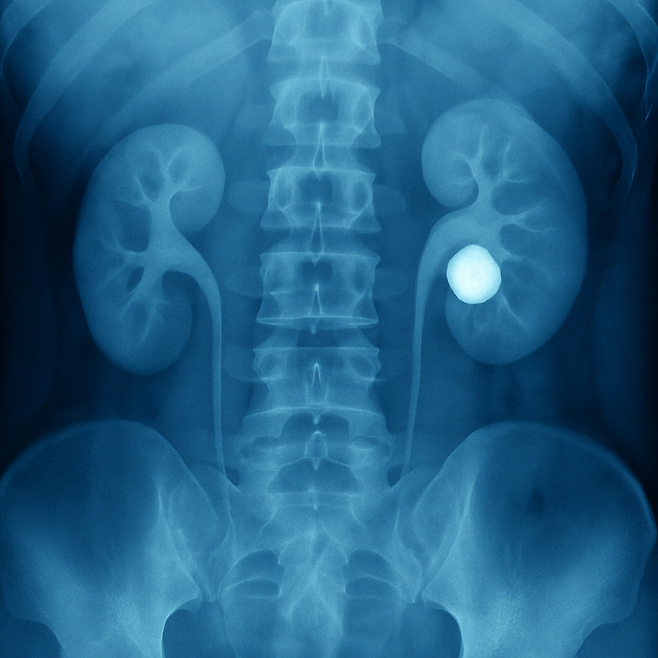

신장결석이란?

신장결석은 소변 속의 칼슘, 요산 등이신장에서 응집되어 단단한 돌(결석)이 만들어지는 질환입니다.이 돌이 요로(소변길)를 따라 이동하면서극심한 통증을 유발하게 되죠.